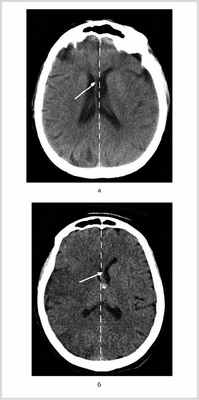

Рис. 2. КТ головного мозга больных с МИИ с фульминантным течением ДС. а — КТ больного П., 6 ч от начала заболевания. На фоне незначительного сужения конвекситальных субарахноидальных борозд левого полушария отмечено смещение срединных структур вправо на 4 мм (указано белой стрелкой, пунктиром показана средняя линия); б — КТ больного В., 8 ч от начала заболевания. На фоне незначительного сужения конвекситальных субарахноидальных борозд и минимальной гиподенсивности правого полушария отмечено смещение срединных структур влево на 2,5 мм.

Прогредиентное течение ДС наблюдалось у 54 больных. У этих пациентов отсутствовала поперечная дислокация головного мозга в первые 24 ч от начала заболевания, однако при повторной КТ головного мозга на 2-е сутки было отмечено развитие поперечной дислокации до 7 мм и более (в среднем 10 мм) (см. рис. 1). При госпитализации уровень бодрствования соответствовал оглушению у 44 (81%) больных, сопору — у 10 (19%). Угнетение уровня бодрствования развивалось в промежуток от 24 до 48 ч от развития инсульта, а на 3—4-е сутки уровень бодрствования у всех больных соответствовал коме (см. рис. 3). При повторной КТ на 3—4-е сутки латеральная дислокация в среднем составила 16 мм. Из 54 больных с прогредиентным течением ДС прооперировали 20 пациентов. Летальность у оперированных больных составила 45%, у неоперированных — 100%.